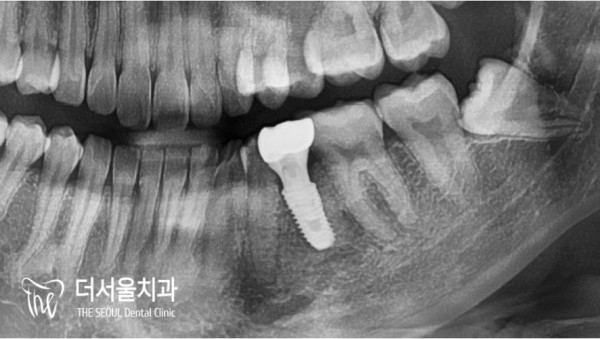

파노라마 사진을 보면 주변 치조골이 유난히 검게 보입니다.

심한 염증으로 치조골이 소실된 것으로 확인됩니다.

If you look at the panoramic picture, the alveolar bone around it looks exceptionally black.

It is confirmed that the alveolar bone has been lost due to severe inflammation.

예상보다 골소실과 염증이 아주 심한 상태였습니다.

치아까지 흔들리는 아주 안좋은 상태인데요. 신경치료를 하다가 중간에

멈추게되면 더욱 심각한 상태로 악화될 수 있습니다.

신경치료 중단 후 2년이나 지난 시점이었기 때문에

자연치아를 살릴 방법이 없어, 임플란트를 결정하였습니다.